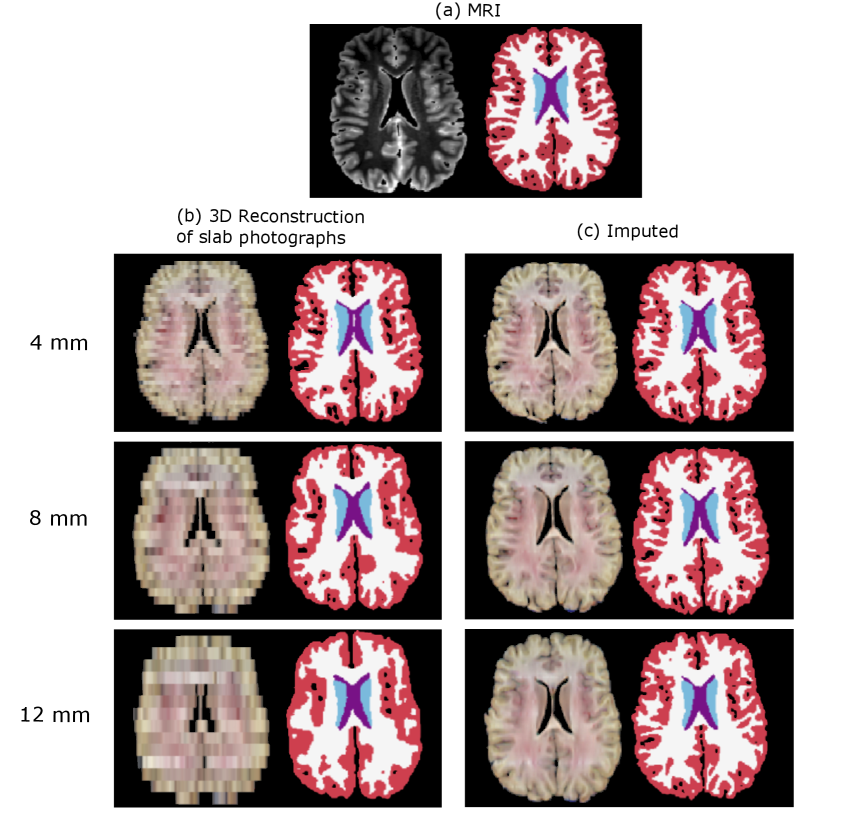

Figure 2 shows the original reconstructions from our previous work and the outputs of our new imputation method on two sample specimens from the UW (Panela) and MADRC datasets (Panel b). At 4 mm thickness, larger brain regions can still be distinguished on the original 3D reconstructions of slab photographs (e.g., thalamus, ventricles). However, as slab thickness increases, the 3D reconstructions appear coarser, with reduced definition of these anatomical regions. In contrast, the cortical and subcortical regions are better defined in the reconstructions generated by our imputation method (Figure  2.b). The improvements from our method are particularly evident on reconstructions from thicker slabs (8-12 mm), especially in the depiction of the cortical folding, which appears much less voxelated – truly bringing the white matter and pial surfaces to life.

Figure 5, and Supplementary Figure S 3, show the segmentation results for two sample cases from the UW and MADRC datasets, respectively. Increasing the slab thickness degrades the segmentation performance on the baseline photo stacks, with the largest errors observed in the cortical and white matter regions, compared to the gold-standard segmentations. This is noticeable, e.g., in Figure 5b (12 mm), where the segmentation map shows a blocky appearance, with a discontinuous cortical ribbon and holes along the sulcal banks and gyral crowns. A similar effect is observed in the segmentations from the MADRC example (Figure S 3b). Our imputation method greatly improves the segmentation detail in both datasets (Figure 5c and Figure S 3c).

Figure 5: Axial views of automated segmentations on one example from the UW dataset at three slab thicknesses (4, 8, 12 mm). (a) Gold-standard segmentation from the MRI. (b) Segmentations on the 3D reconstructions from the original slab photographs. (c) Segmentations from imputed reconstructions.